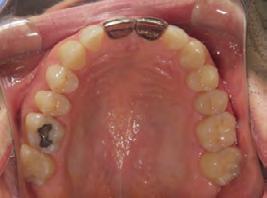

Clinical evaluation showed a mild Class III skeletal pattern with a constricted maxilla, mildly dolichofacial and straight

profile (Figure 1). Full adult dentition was present with all third molars extracted. Maxillary and mandibular incisors were normoclined. The maxillary midline coincided with the facial midline, and the mandibular midline was 2 mm to the right of the facial midline. There was a 2 mm to 5 mm lateral open bite on the right side from the second molar to the lateral incisor, and the maxillary occlusal plane was canted to the left of the interpupillary line. A lateral tongue thrust into the open bite was noted on swallow.

The right side was in posterior crossbite and there was an edge-to-edge anterior bite with wear on the maxillary central incisors. Mild gingival recession was noted, but soft tissue was generally within normal limits. CBCT analysis found no radiographic evidence of osteoarthritis in the TMJ joints, nor osseous or apical pathology involving the maxillary or mandibular teeth. His airway was not constricted. Initial report from the myofunctional therapist indicated that the patient never developed a mature swallow sequence and had a bilateral posterior tongue thrust.

Figure 1. Initial records.